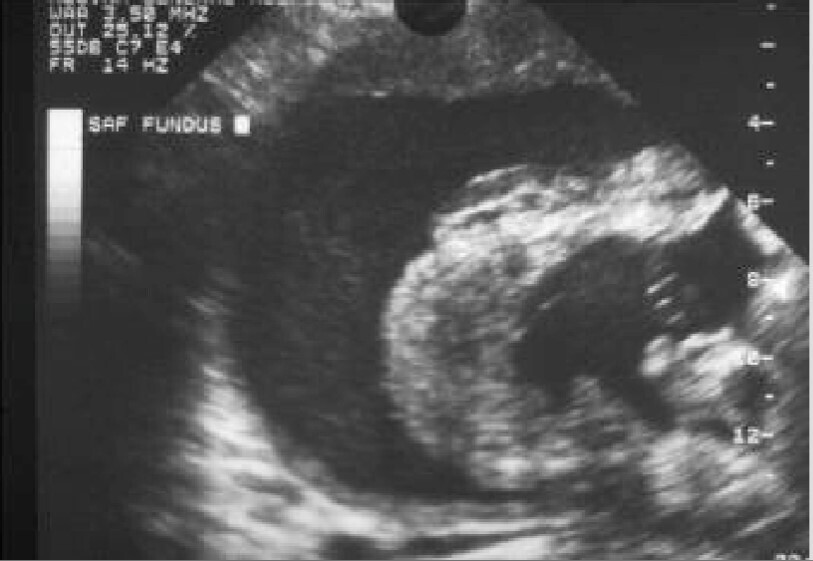

Le tableau de môle hydatiforme est caractéristique avec une patiente qui présente des signes de grossesse exacerbés : vomissements, tension mammaire importante, utérus augmenté de volume, métrorragies. L’échographie retrouve une image hétérogène intra-utérine en « tempête de neige » avec un dosage de gonadotrophine chorionique humaine (HCG) le plus souvent > 100 000 UI/L

Vous poursuivez votre examen. L’échographie endovaginale vous montre :